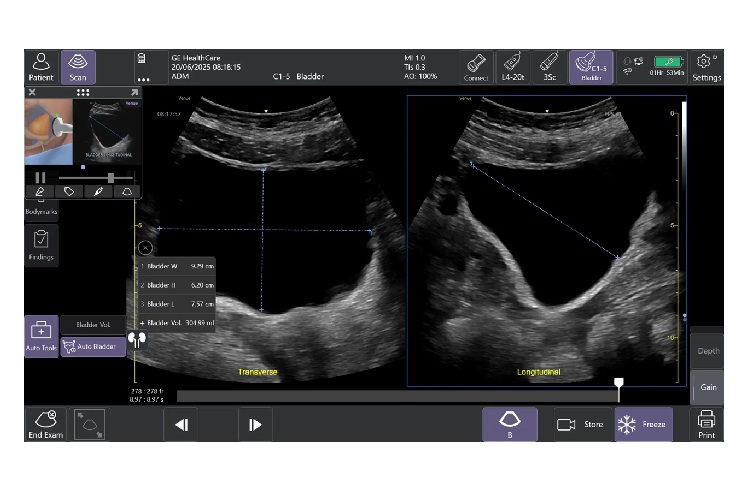

「Auto Bladder Volume」は、ぼうこうの容積を半自動で計測するツール。救急外来や集中治療室、手術後、病棟などでの活用を想定しており、侵襲的な処置を行うことなくスピーディーに効率的なぼうこう容積評価ができる。